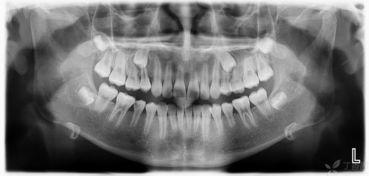

现在,让我们来看看这个视频吧!视频中,一位专业的口腔医生详细讲解了成人双排牙恢复的过程。首先,医生会通过X光片检查牙齿情况,确定治疗方案。根据具体情况,医生会采取不同的矫正方法。